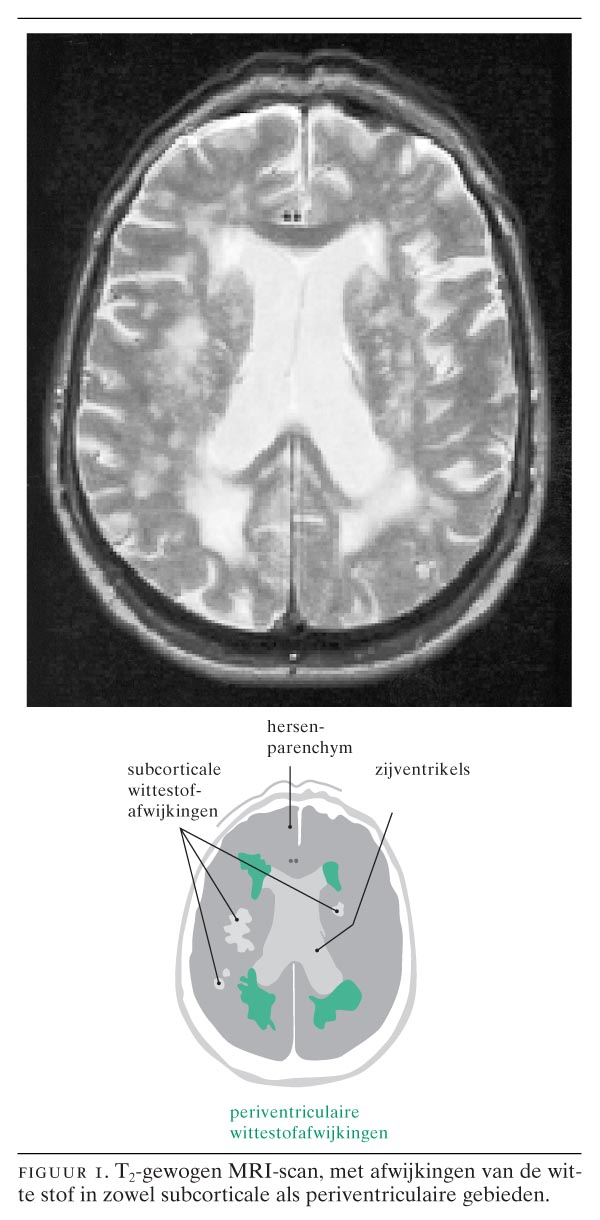

Myeline is het hoofdbestanddeel van de witte stof, maar ook grijze stof bevat veel myeline, doordat er gemyeliniseerde vezels naartoe of doorheen lopen. Zo is de thalamus een van de eerste hersen-structuren die myeliniseert.1 Op T1-gewogen opnames heeft de witte stof myeline een hoog signaal; op T2-gewogen opnames is de normale witte stof donker.. Amsterdam, november 2001, Met belangstelling lazen wij het caput selectum van De Leeuw et al. (2001:2067-71).Wij zijn het volledig met de auteurs eens dat het hier gaat om een stille epidemie en dat wittestofafwijkingen (WSA) een uitdaging bij de behandeling van vasculaire risicofactoren zijn.